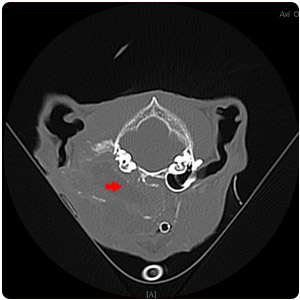

| 腹腔腫塊(紅)、腹水(黃) |

腹水(紫)、腹部腫塊(紅)、子宮殘段(黃) |